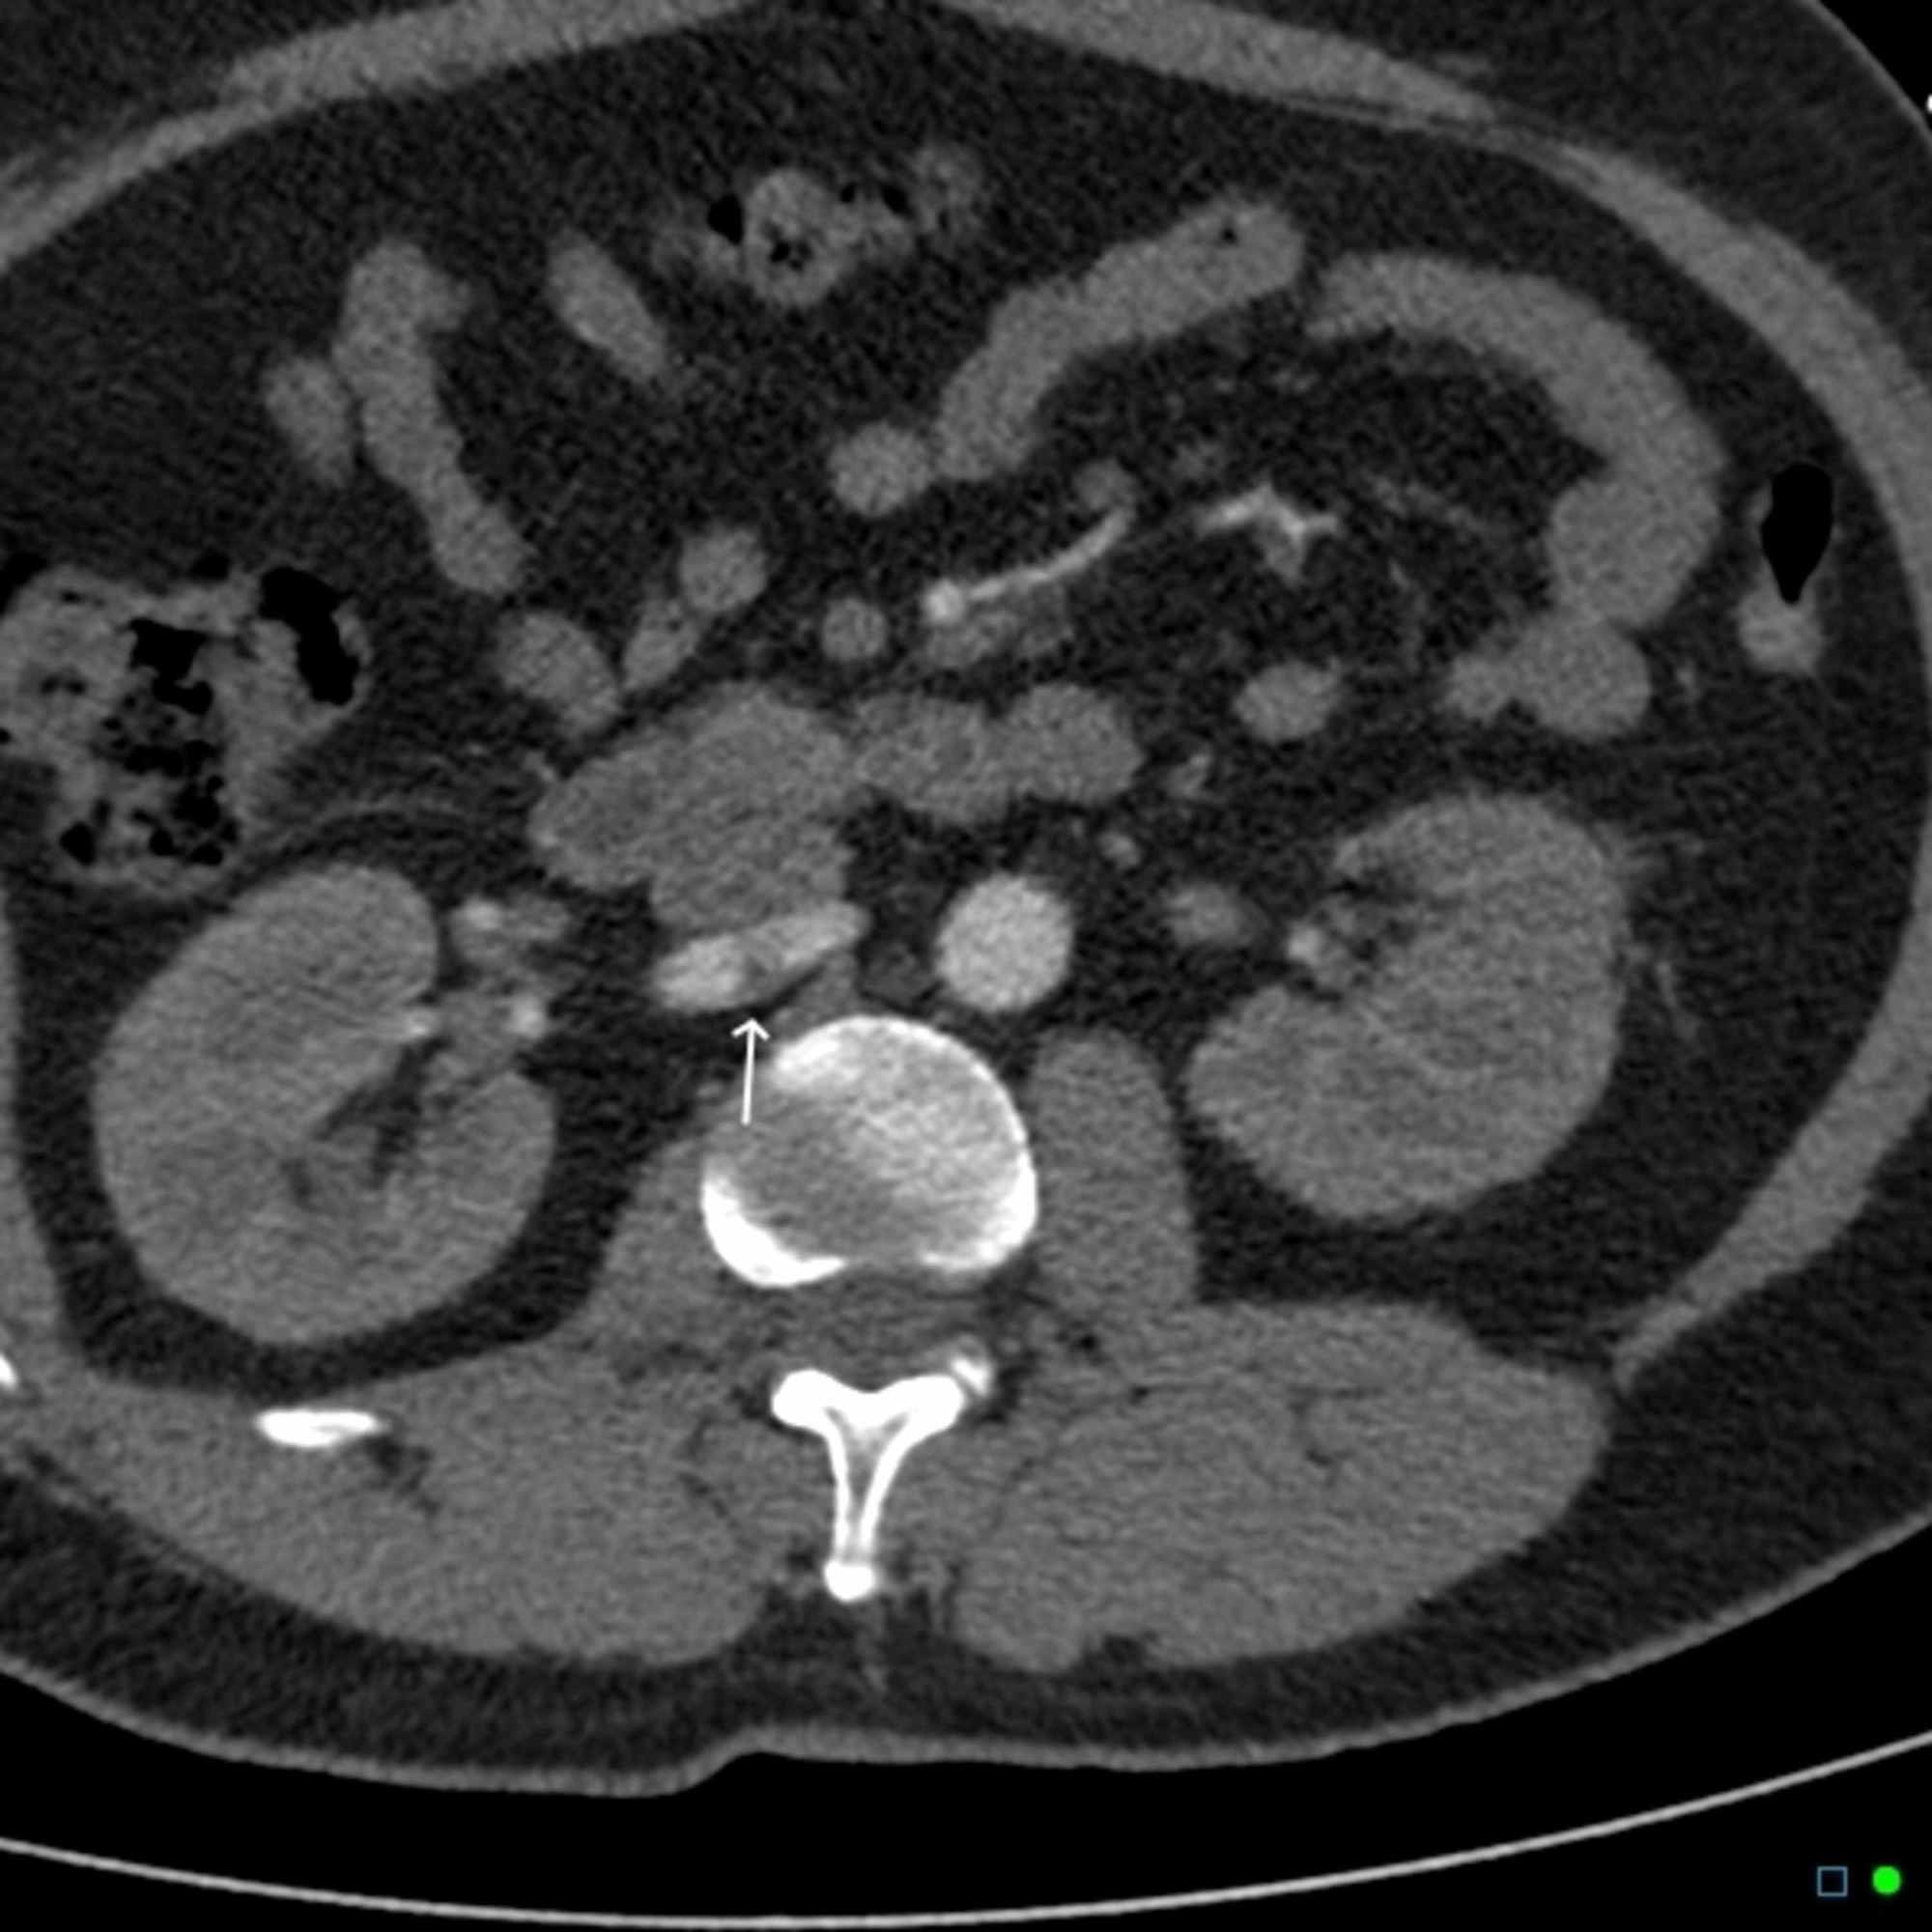

Figure 1 from Spontaneous renal artery dissection. Semantic Scholar

Figure 2 from Renal Artery Dissection in an Emergency Department Case Report Renal Artery Dissection Spontaneous renal artery dissection may occur spontaneously or secondary to local changes. In this case the renal infarction arose from a rare cause: These dissections can occur due. Spontaneous dissection of the renal artery. It is unusual for somatic type pain to actually. Renal artery (ra) dissections remain a rare and poorly understood disease process [1, 2]. Fourteen patients with. Case Report Renal Artery Dissection.